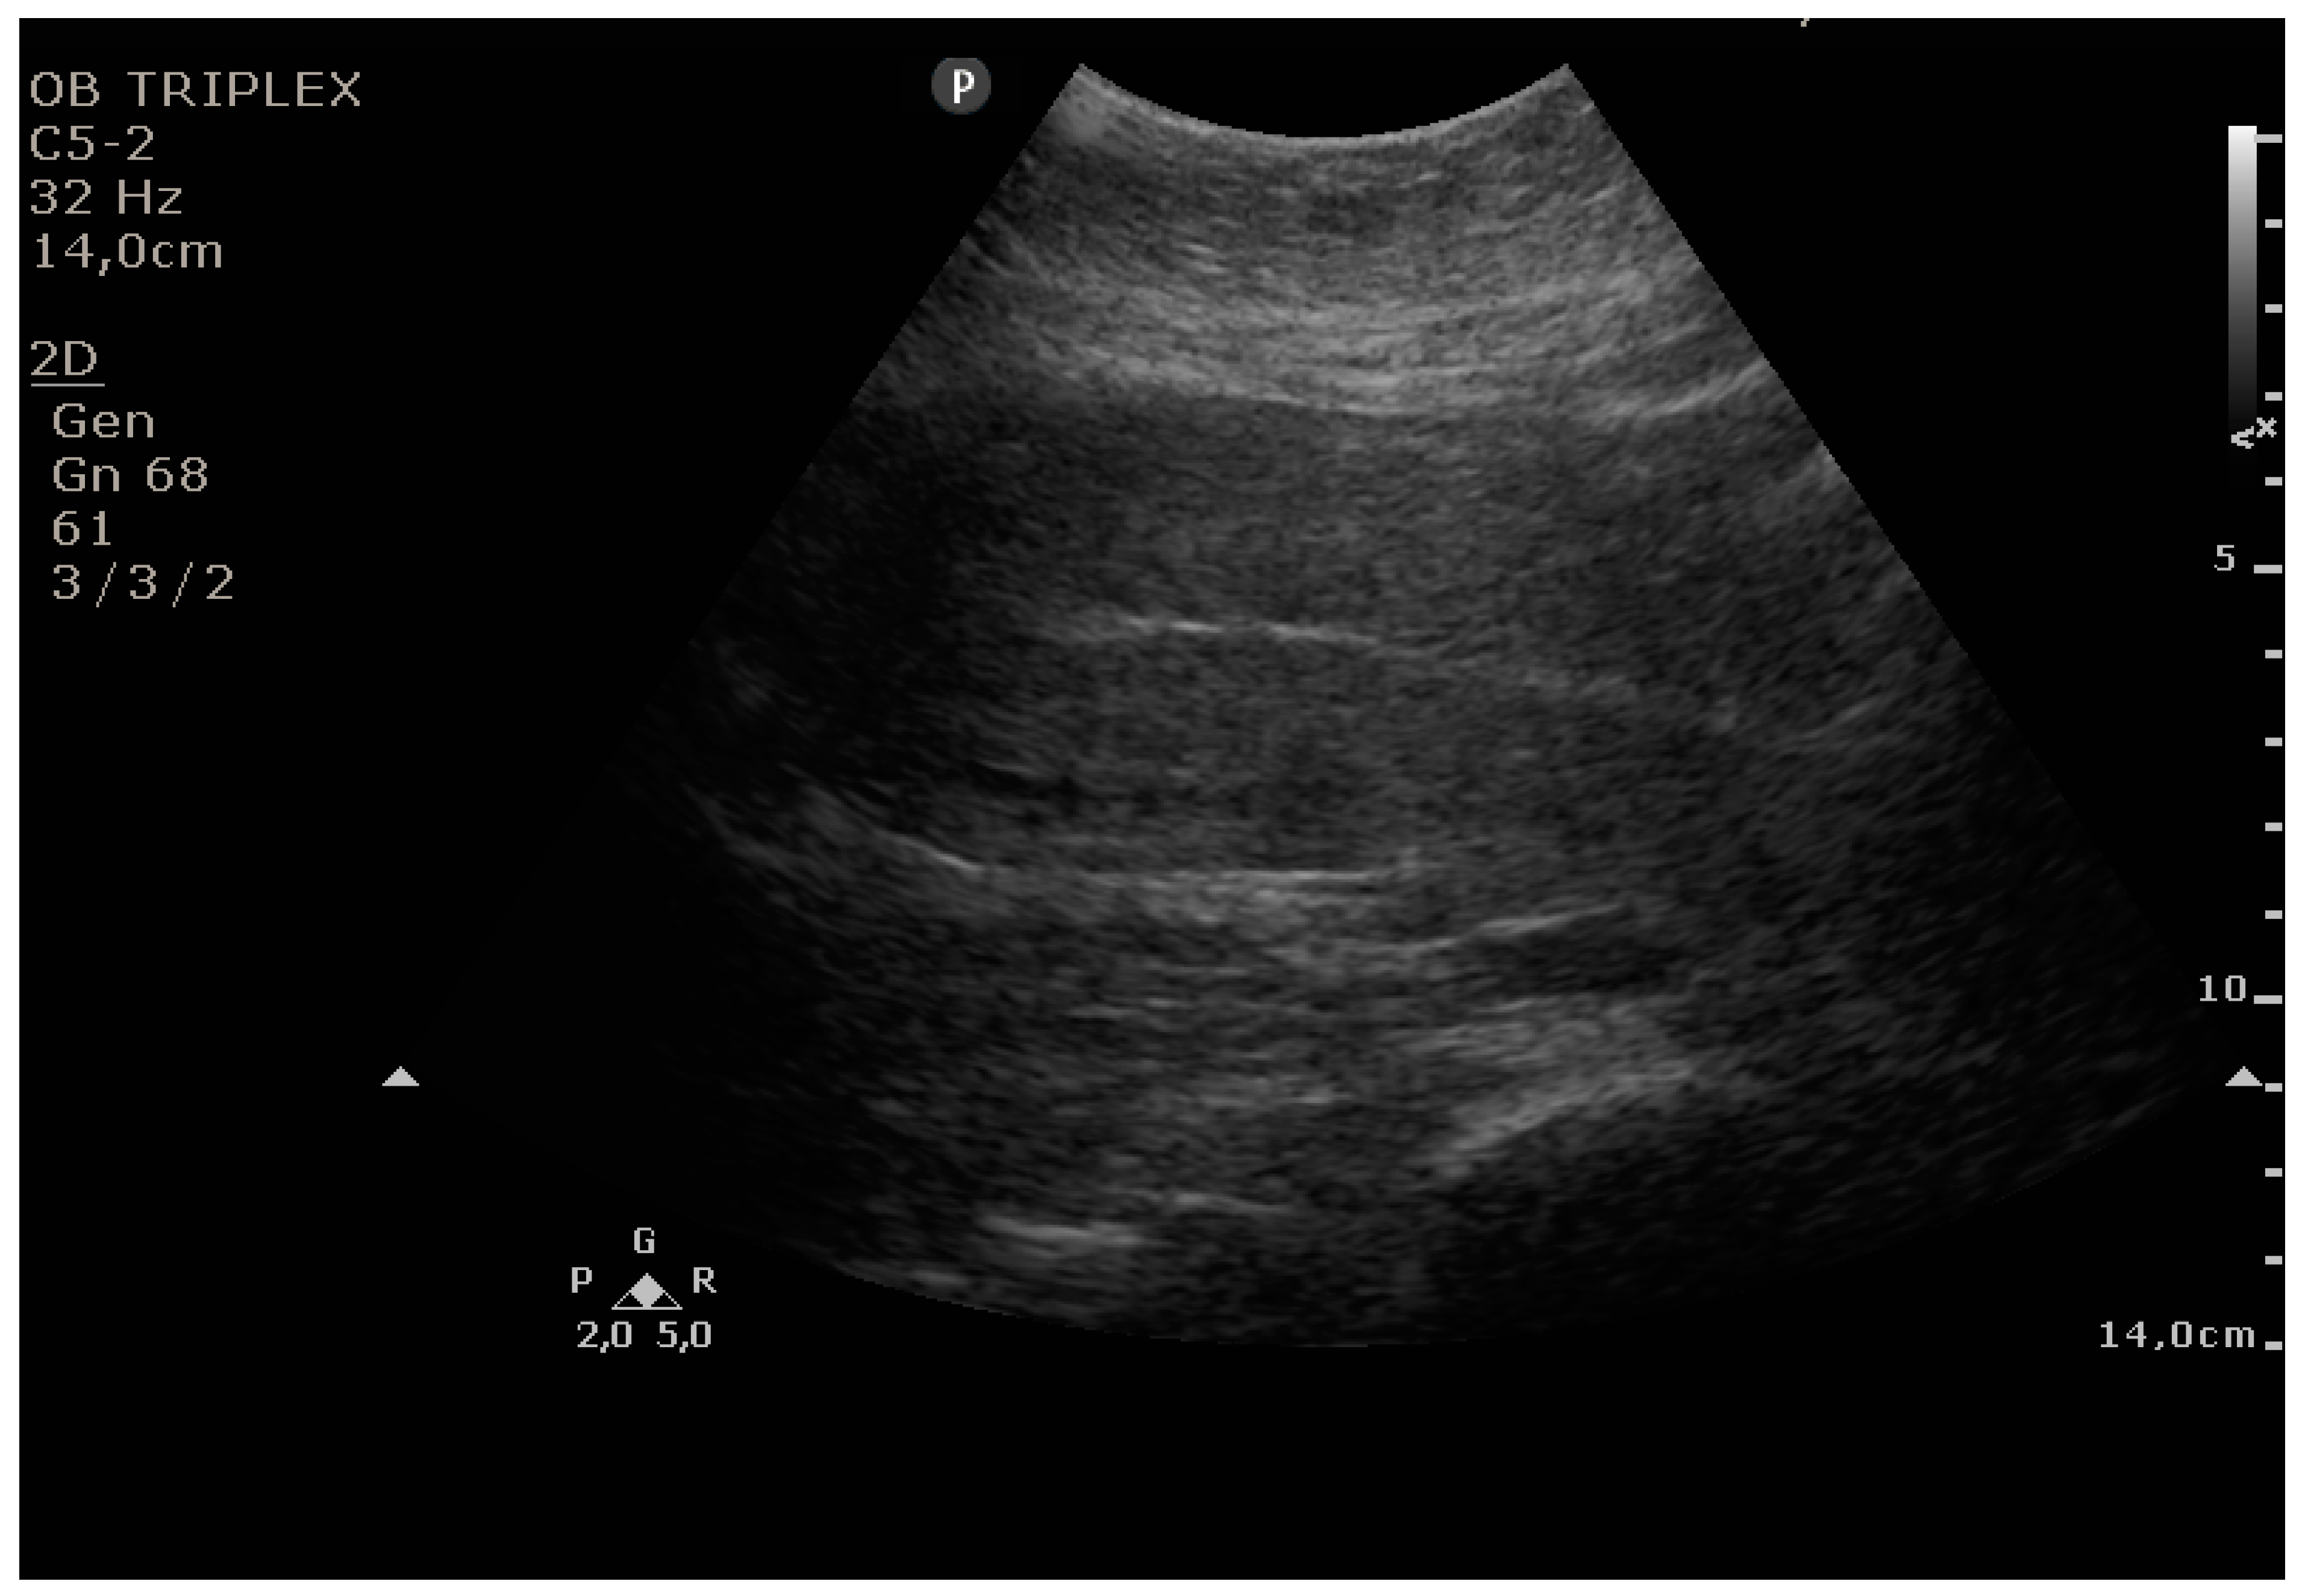

The PUUS method evaluates the proportion of the endometrial length occupied by blood or debris, as follows (Figure 1, Figure 2, Figure 3, Figure 4 and Figure 5):

Grade 4: over three-quarters of the endometrial length occupied by blood or debris.

Figure 5. Grade 4: over three-quarters of the endometrial length occupied by blood or debris.